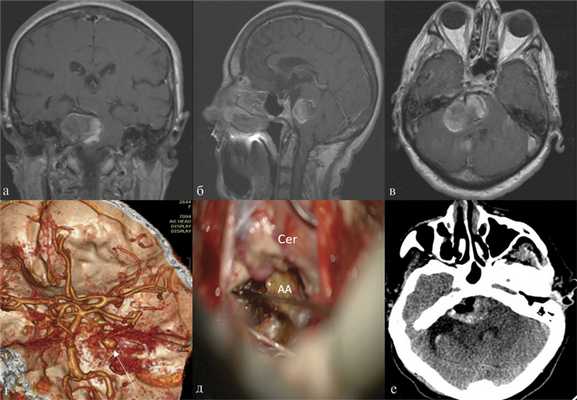

В 2 случаях в связи с сохраняющейся симптоматикой был выполнен второй этап оперативного вмешательства, заключавшийся в декомпрессивной трепанации задней черепной ямки и удалении мешка аневризмы, оказывающего компрессионное воздействие на ствол головного мозга (рис. 2). Рис. 2. Гигантская аневризма правой верхней мозжечковой артерии. а, б, в — МРТ в коронарной, сагиттальной и аксиальной проекциях, режим Т1 В.И. Визуализируется мешок гигантской аневризмы, грубо сдавливающий ствол головного мозга; г — СКТ-ангиография, белой стрелкой указана заполняющаяся часть аневризмы; д — этап операции удаления тромботических масс из полости аневризмы. Интраоперационное фото. АА — мешок аневризмы, Cer — мозжечок; е — СКТ головного мозга после операции, отмечается значительное уменьшение размеров аневризматического мешка с уменьшением компрессии ствола.